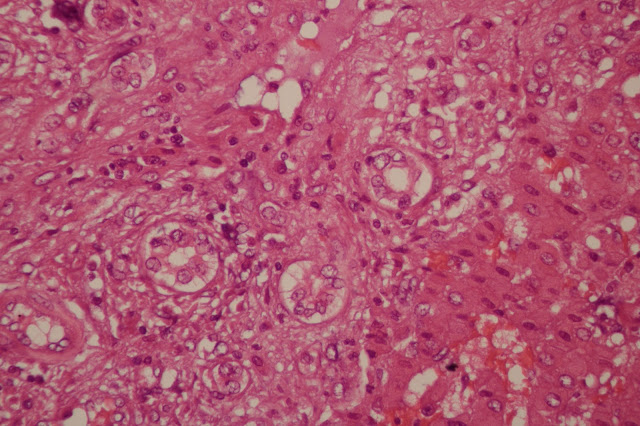

With input from our Peds Path collaborators, we have diagnosed this lesion as a mesenchymal hamartoma of the liver (MH). An important consideration for this lesion is that an undifferentiated embryonal sarcoma (UES) can arise within this hamartomatous process. This is indeed what we identified in this case. As you'll see below (40x objective, HPF), we have found areas with significant cytologic atypia and multiple mitoses (we maxed out at 5 per HPF).

| Multiple mitotic figures are present in this area of atypical stromal cells. |

| Significant stromal cell atypia, getting towards anapastic. |